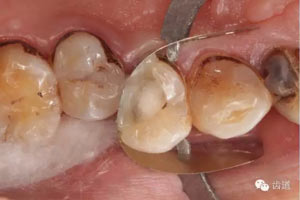

處理:去除暫封物,超聲根管蕩洗,清除氫氧化鈣糊劑,干燥根管,拍片顯示2506牙膠尖適合,根管內(nèi)放置AH plus,熱牙膠連續(xù)波根管充填。

數(shù)碼x攝影顯示:近中頰根及腭根根管充填恰填,遠(yuǎn)中根管有遺漏。

顯微鏡下反復(fù)探查根管,未探及遺漏根管口,放置棉球,zoe暫封。轉(zhuǎn)診上級(jí)醫(yī)生處理。